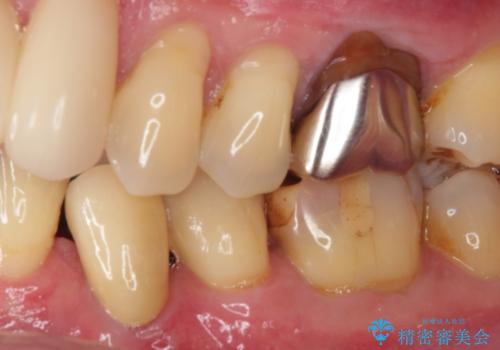

- 奥歯の虫歯と前歯のデコボコや突出感を気にして来院された患者様です。

矯正治療後は、奥歯の虫歯や銀歯を補綴・修復治療することとしました。